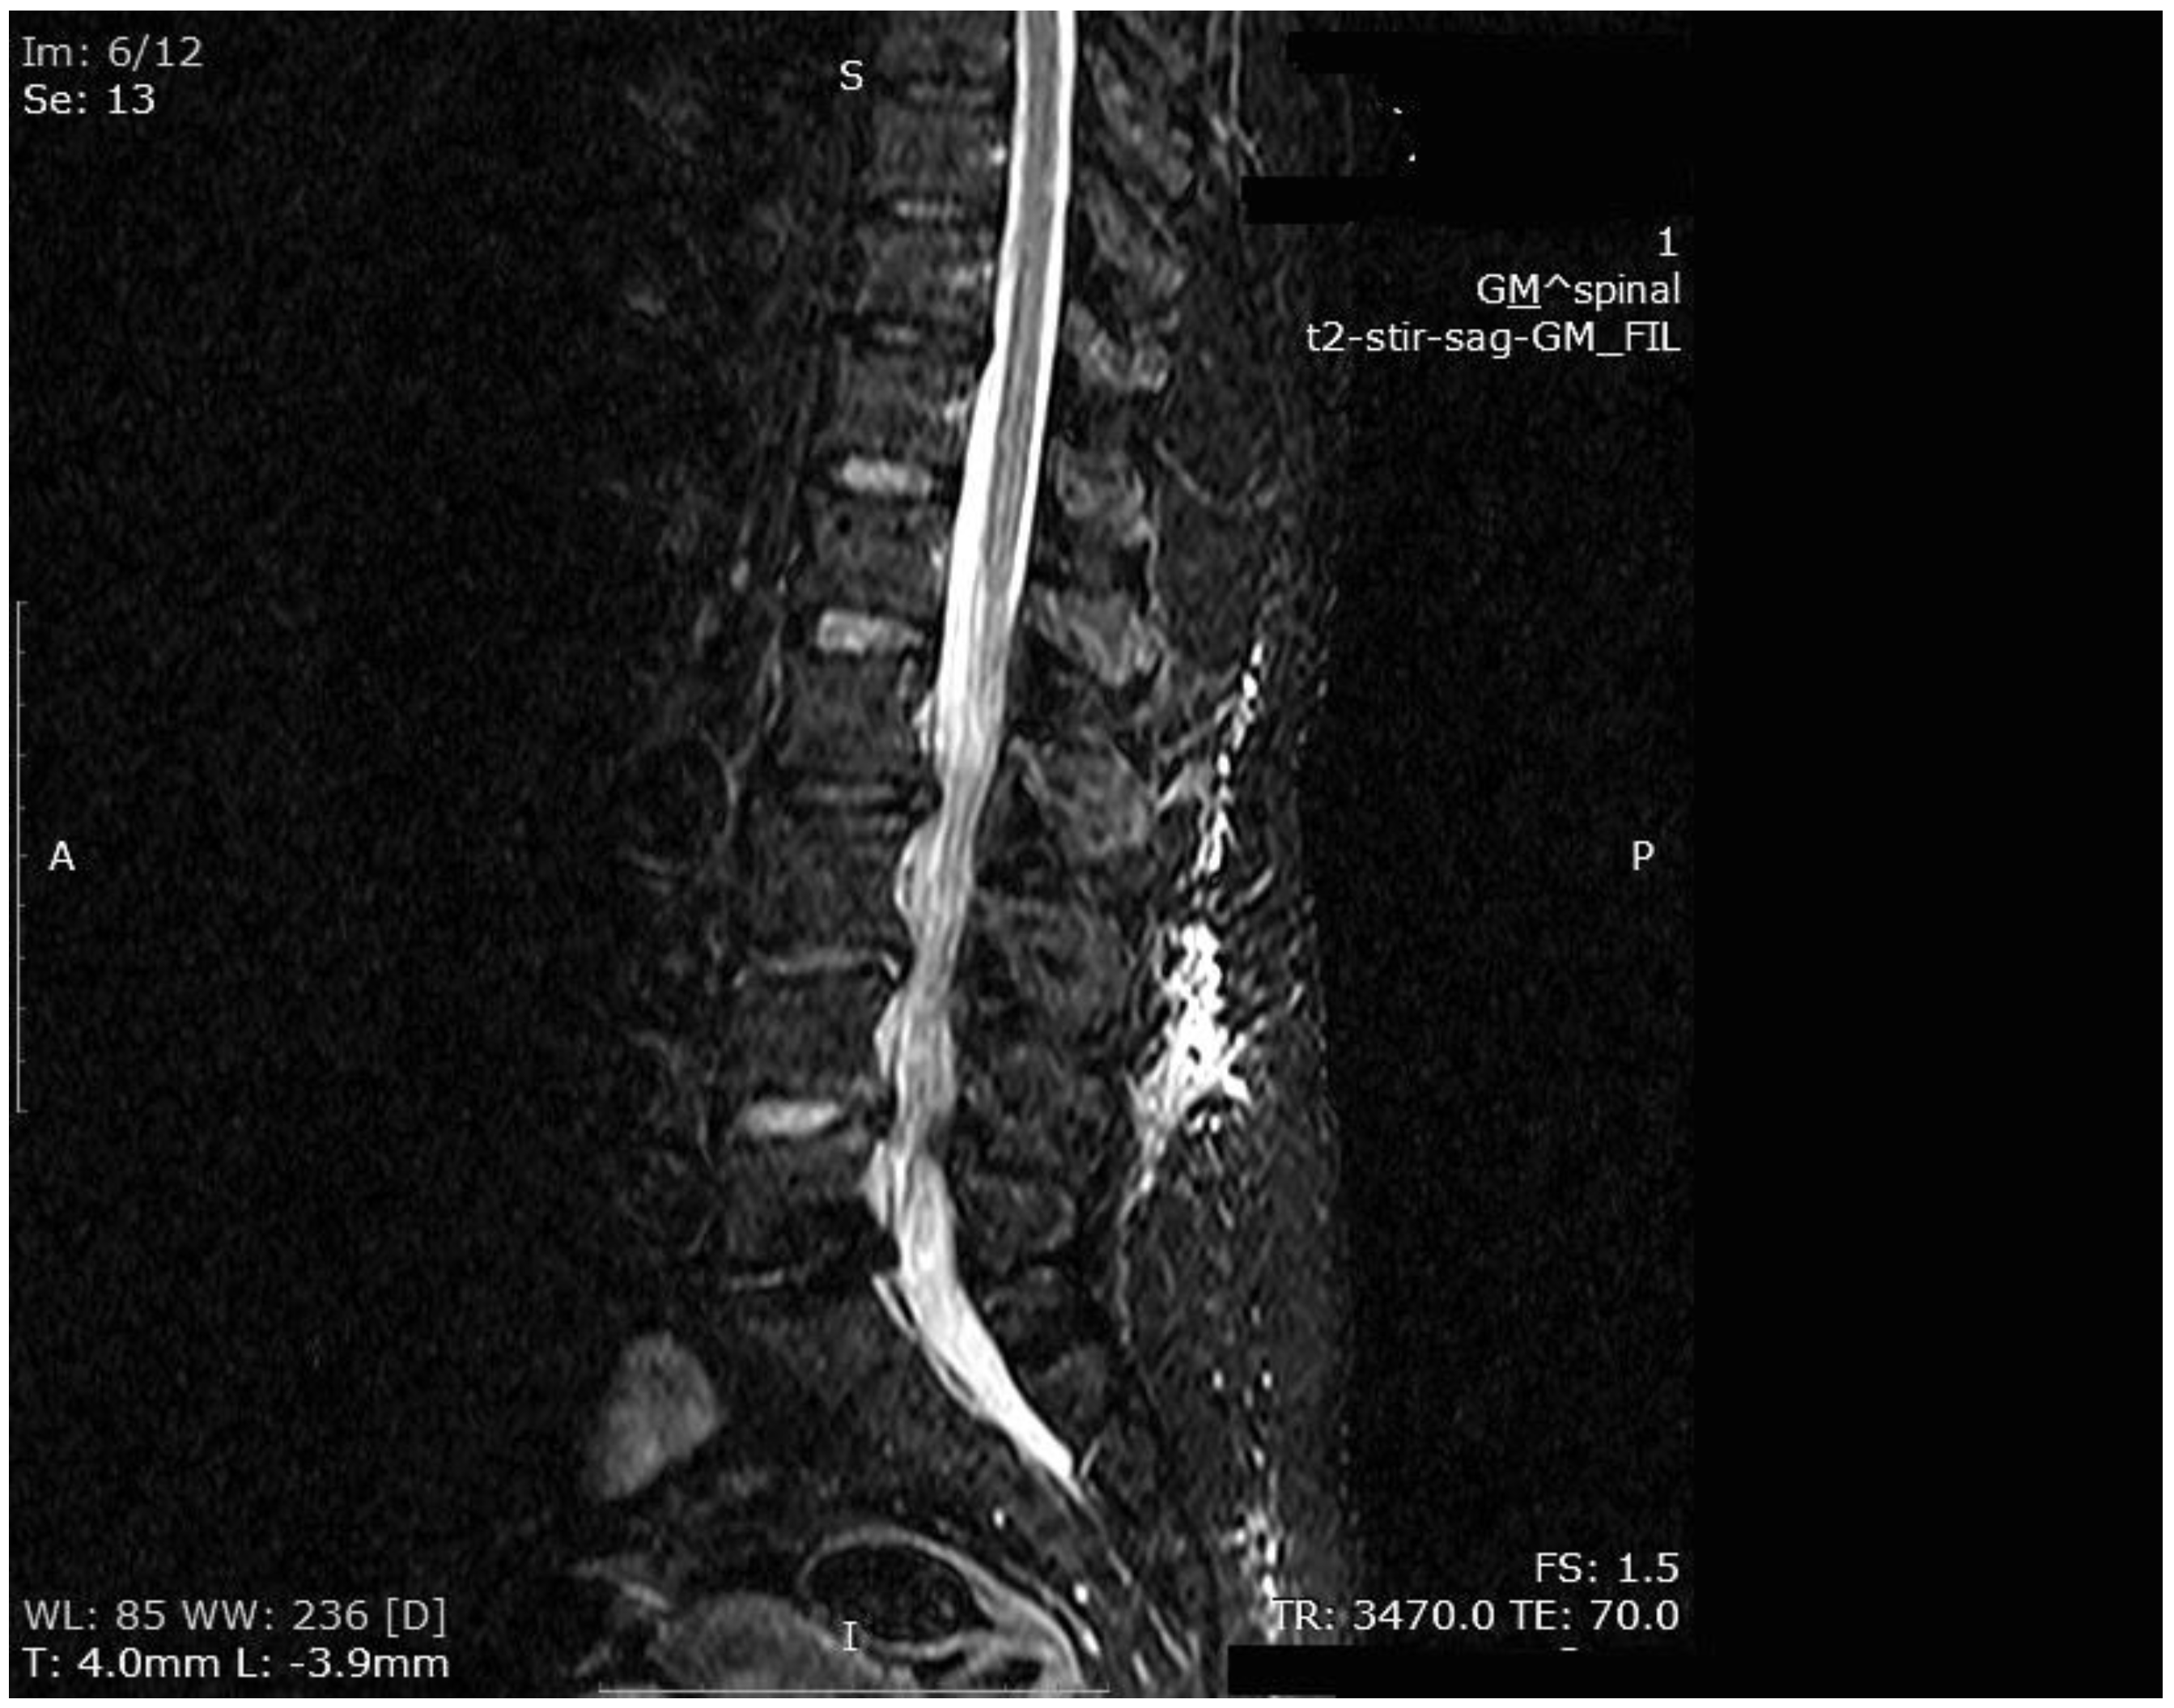

Figure 5. MR imaging scan showing inflammatory infiltrates at the end of HBO2 treatment.

The mean number of total HBO2 sessions was 33 (±18.5) sessions. The HBO2 treatment was tolerated well by all patients except two. One patient had to receive analgesics (non-steroidal anti-inflammatories) before HBO2 sessions because she had severe back pain, and in one patient the treatment was interrupted for five days because of minor middle ear barotrauma. Improvements in clinical evaluations and laboratory findings were observed in all cases at the end of the HBO2 therapy. The mean erythrocyte sedimentation rate (ESR) value reduced from 76.1 (range, 6–129) to 45.7 (range, 5–81) mm/h, and the mean C-reactive protein (CRP) concentration reduced from 82.9 (range, 14–202) to 17.5 (range, 1–49.5) mg/L (normal limits; ESR: <20 mm/h, CRP: 0–5 mg/L). Infection resolution was adequately achieved in 12 of 13 patients on MR imaging at the end of HBO2 treatment or during the first month of follow-up (Figure 3, Figure 4 and Figure 5). There was no significant improvement in one patient. To extend the total clinical follow-up period up to three years (mean: 11 months; range, 1 month–3 years), telephone interviews were conducted to determine any recurrence of symptomatic clinical infection. No recurrence of infection, spinal instability, or deformity was seen in any patients.